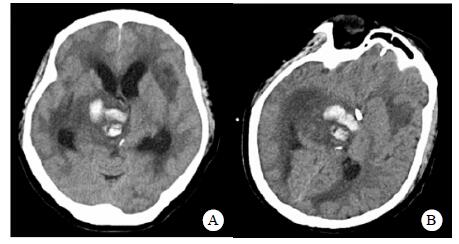

转入ICU后呼吸机辅助通气、甘露醇100 mL/8 h静滴脱水、头孢呋辛1.5 g/12 h静滴抗感染,肠内营养等支持治疗。当晚血常规:白细胞13.3×109/L,中性粒细胞百分比85.3%,C反应蛋白17.1 mg/L,降钙素原0.64 ng/mL。脑室外引流术后次日血化验:白细胞16.6×109/L,中性粒细胞百分比92.8%,C反应蛋白78.4 mg/L;从脑室外引流管留取脑脊液检验:有核细胞6×106/L,红细胞1 960×106/L,蛋白含量1.717 g/L,葡萄糖4.72 mmol/L,细菌培养阴性,涂片未找到细菌;复查头颅CT示:脑室扩张好转,右侧丘脑、左侧岛叶病变伴出血(图 2);胸部CT示,两肺间质性肺炎下叶为著,较前(2019年6月21日)部分好转(图 3)。考虑到炎症指标升高,遂改哌拉西林他唑巴坦3.375 g/12 h静滴抗感染。此后经脑室外引流管反复留取脑脊液送检涂片及培养均阴性。术后第5天行“导航下立体定向颅内病灶活检术+双侧omaya囊置入术”,术中穿刺液呈黄色黏稠脓性,考虑脑脓肿,留取脓液送高通量测序(next-generation sequencing, NGS),并升级为美罗培南2 g/8 h联合利奈唑胺0.6 g/12 h静滴抗感染治疗。术后第7天患者突发血压升高、瞳孔不等大,昏迷程度加深;急查头颅CT示,双侧脑室钻孔引流术后改变,双侧侧脑室引流管走形区出血伴血肿形成;右侧丘脑区积液、积血,双侧脑室积血新发(图 4),甘露醇加量至250 mL/8 h联合地塞米松5 mg/6 h静滴加强脱水;当日术中脓液高通量测序结果回报:皮疽诺卡菌(序列数52 867个)、支气管戈登菌(序列数10个)。确诊脑诺卡菌病,抗菌治疗方案改为亚胺培南西司他丁0.5 g/6 h静滴,联合利奈唑胺0.6 g/12 h和复方磺胺甲恶唑片(0.48 g/片)3片/6 h口服。此后患者仍伴低热,炎症指标呈上升趋势。术后2周患者再次突发血压升高、瞳孔不等大、对光反射消失、神志深昏迷,急查头颅CT示再发脑疝(图 5),急诊行“去骨瓣减压术+脑内血肿清除术”,术后患者仍呈深昏迷状态,双侧瞳孔散大、对光反射消失,次日自动出院。

| 双侧脑室钻孔引流术后改变,双侧侧脑室引流管走形区出血伴血肿形成;右侧丘脑区积液、积血,双侧脑室积血新发 图 4 患者2019-10-06头颅CT结果 |

| 双侧侧脑室引流管走形区出血伴血肿形成;右侧丘脑区积液、积血,脑室积血;左引流管旁血肿较前(2019-10-06)增大,脑室积血增多,中线右移。左岛叶及颞叶斑块状低密度影 图 5 患者2019-10-13头颅CT平扫结果 |